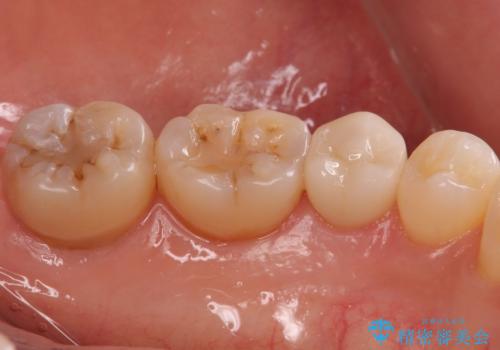

- 左下7 仮歯+e-maxクラウン:11,000円+77,000円費用は治療当時の料金となります

今回の場合、虫歯の大きさが大きく本来であれば歯茎に対しても治療をすることが検討されケースですが、ご希望されなかったため被せ物のみでの治療となりました。

出産前後では口腔内環境が変わることが多々あります。

是非落ち着いたタイミングで検査を受けることをお勧めします。